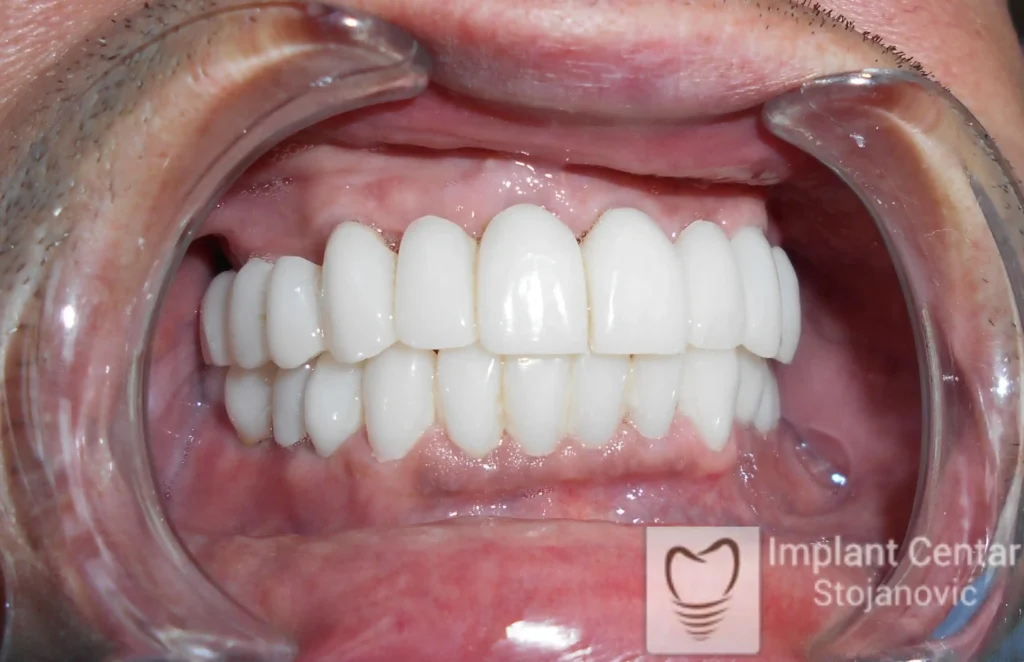

Na slikama 1, 2, 3 , 4  i  5 prikazan je izgled pacijenta pre početka terapije. Nakon detaljne kliničke i radiološke analize, doneta je odluka o vađenju zuba loše biološke vrednosti, dok su bezuba polja sanirana ugradnjom dentalnih implantata.

Nakon ugradnje implantata i pripreme preostalih zuba, pacijentu su izrađene fiksne privremene krunice, čime je postignut eugnatan zagriz već nakon jednog dana (slika 8, 9 i 10). Tokom perioda osteointegracije, pacijent se postepeno privikavao na novi položaj vilica i zagriz.

Po završetku perioda integracije, izrađeni su definitivni cirkonijum-keramički mostovi, čime je postignuta potpuna rekonstrukcija zagriza, kao i značajno poboljšanje estetike i oralne funkcije (slika 12, 13, 14 i 15).

Pacijent je izrazito zadovoljan postignutim rezultatom, kako funkcionalno, tako i estetski, uz značajno poboljšanje kvaliteta svakodnevnog života.